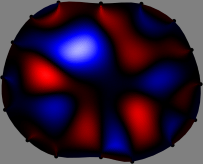

To explain the FER method, we closely examine the correlations among column vectors of the sensitivity matrix 𝕊𝕊\mathbb{S}, described in Fig. 2. The correlation between 𝐒ksubscript𝐒𝑘{\bf S}_{k} and 𝐒subscript𝐒{\bf S}_{\ell} can be expressed as

for i=1,,16𝑖116i=1,\cdots,16[23]. This shows that the column vector 𝐒ksubscript𝐒𝑘{\bf S}_{k} is like an EEG (electroencephalography) data induced by dipole sources with directions uj,j=1,,16formulae-sequencesubscript𝑢𝑗𝑗116\nabla u_{j},j=1,\cdots,16 at locations ΔksubscriptΔ𝑘\Delta_{k}. Given that two dipole sources at distant locations produce mutually independent data, the correlation between 𝐒ksubscript𝐒𝑘\mathbf{S}_{k} and 𝐒subscript𝐒\mathbf{S}_{\ell} decreases with the distance between ΔksubscriptΔ𝑘\Delta_{k} and ΔsubscriptΔ\Delta_{\ell}. Fig. 2 shows a few images of the correlation 𝐒k,𝐒(|𝐒k||𝐒|)1subscript𝐒𝑘subscript𝐒superscriptsubscript𝐒𝑘subscript𝐒1\left\langle\mathbf{S}_{k},\mathbf{S}_{\ell}\right\rangle(|\mathbf{S}_{k}||\mathbf{S}_{\ell}|)^{-1} as a function of \ell for four different positions ΔksubscriptΔ𝑘\Delta_{k}. The correlation decreases rapidly as the distance increases. In the green regions where the correlation is almost zero, 𝐒subscript𝐒{\bf S}_{\ell} is nearly orthogonal to 𝐒ksubscript𝐒𝑘{\bf S}_{k}.